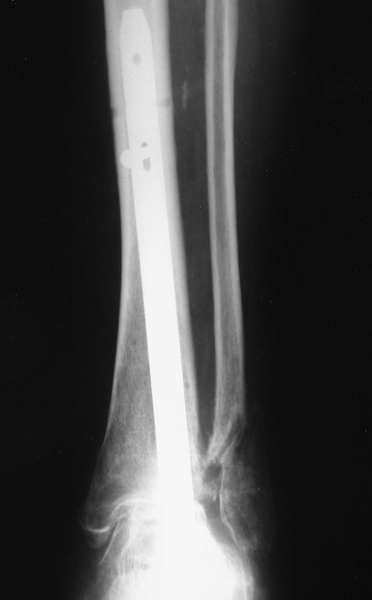

Можно: 65-летняя пациентка, оперирована по поводу несросшегося в гипсе перелома лодыжек с патологической вальгусной установкой стопы и выраженным нарушением опрной функции. Оперирована через 6 месяцев после травмы. Рентгенограммы через 4 месяца после операции.

Мы бы сделали тоже самое с остатками лодыжек, но артродез, который безусловно показан, выполнили бы закрыто блокируемым штифтом (типа DFN) через пятку. Опороспособность восстановится сразу, артродез (рентгенологический) наступит месяцев через 4-6.

Уважаемый А.Семенистый. Складывается впечатление, что вы выполнили трехсуставный артродез, уж больно длинные блокирующие винты. Не мешают ли они пациентке при ходьбе?

Да конечно винты длинноваты! Мешают ли ходить? Во всяком случае субьективно пациентка удовлетворена. Ходит, естевственно, хуже чеи до травмы, но намного лучше, чем до операции.